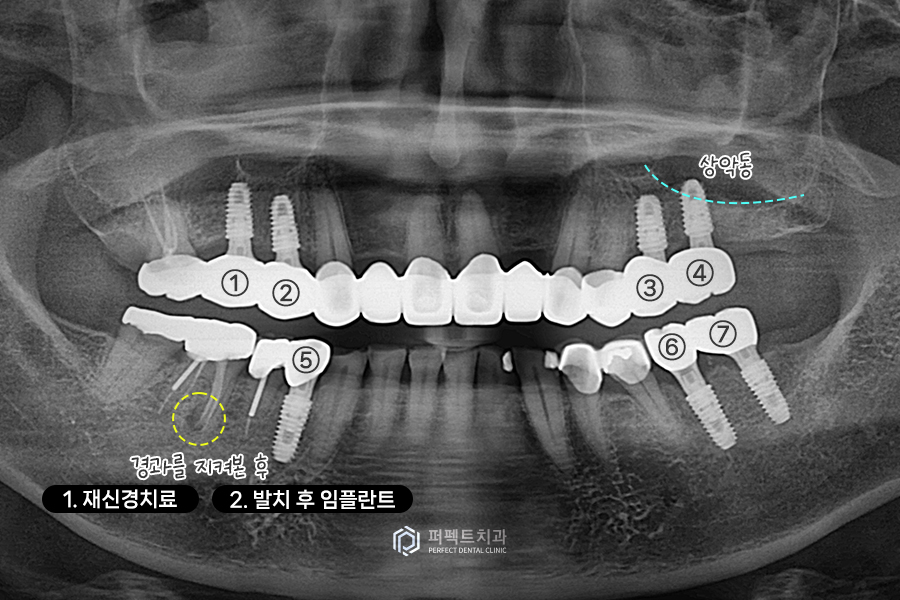

치료 후 사진을 보시면 임플란트가 오른쪽 위에 2개, 왼쪽에 1개, 아래 2개 이렇게 치아가 없는 부위를 수복했습니다. 임플란트가 없는 왼쪽 어금니 부분은 기다렸다가 추후에 식립을 진행했습니다.

왼쪽 임플란트가 없었던 부분에 하나 더 식립을 했습니다. 왼쪽 어금니를 식립한 부분은 상악동이라고 하는 곳이 있는데 이 부분에 뼈가 없어서 기다렸다가 추후에 식립한 경우라고 보시면 될 것 같습니다.

이렇게 어금니는 총 7개의 임플란트를 식립했고, 앞니 보철과 아랫니 부분도 꼭 해야하는 부분은 다시 재치료를 했습니다.

사진 상 체크되어 있는 치아는 염증이 조금 남아있는 치아인데, 이 치아는 경과를 지켜보면서 치료가 필요한 경우 재신경치료나 발치 후 임플란트를 진행하기로 하였습니다.